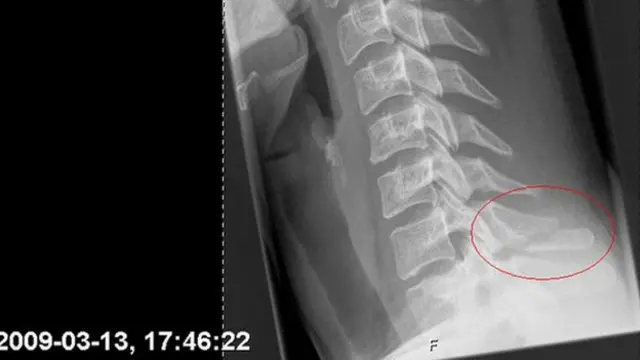

Apesardenise dona bet365encarar mesesdenise dona bet365recuperação usando um colar cervical, a jovemdenise dona bet36528 anos se manteve animada.